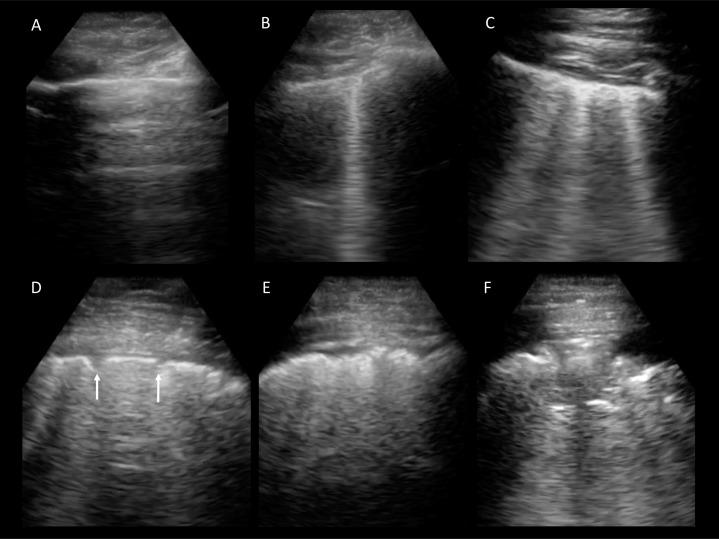

必须了解 2019 年冠状病毒病(COVID-19)大流行的严峻临床背景。意大利正深陷 COVID-19 大流行之中,世界上大多数国家也将很快如此。目前,美国记录的 COVID-19 病例数居世界首位。严重急性呼吸综合征冠状病毒 2(SARS-CoV-2)相关的急性心肌炎在重症监护患者中很常见,且与高死亡率相关。COVID-19 患者经常需要机械支持以实现充分氧合。预计会严重短缺呼吸机。同样令人担忧的是,预计需要大量经过培训的专业人员来护理接受机械通气的患者。超声检查已被证明是识别 COVID-19 的肺部表现和进展的有用工具。肺部超声还可促进机械通气的成功撤机。有经验的超声心动图医师可以轻松掌握肺部、胸膜和膈肌的超声检查。超声心动图在优化液体管理和识别心脏病(包括 SARS-CoV-2 相关的急性心肌炎)方面具有既定作用。心脏病专家、麻醉师、超声技师和所有提供者都应准备好充分发挥自己的技能,以减轻大流行的后果。我们还应准备好进行协作和交叉培训,以根据需要扩大专业服务。在宣布的医疗保健危机中,提供者必须熟悉伦理原则、组织结构、实际应用和有限资源分配的严重性。